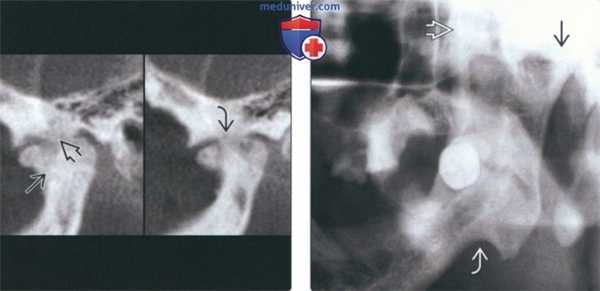

(Слева) На сагиттальной реформатированной КЛКТ определяется анкилоз левого мыщелка. Мыщелок склерозирован, суставное пространство отсутствует в зоне слияния. Височная кость неровная, склерозированная. Суставная ямка уплощена, суставное возвышение отсутствует.

(Справа) На панорамной рентгенограмме определяется костный анкилоз левого ВНЧС. Суставное пространство не визуализируется, форма мыщелка плохо различима. Венечный отросток удлинен, антегониальная вырезка углублена.